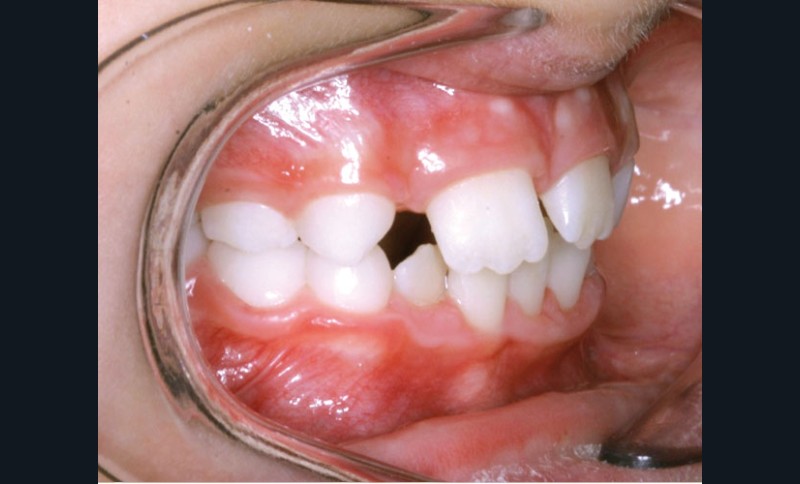

La décision thérapeutique s’est orientée dès cette consultation vers la fermeture des espaces d’agénésie et l’extraction de la 52 a été réalisée à ce stade pour respecter la symétrie antérieure et favoriser l’évolution symétrique des deux canines en position d’incisives latérales.

Les vues endo-buccales après extraction de 52 montrent des relations occlusales de classe II, un léger encombrement incisif mandibulaire et une tendance à la fermeture spontanée des espaces des incisives latérales confirmant le choix thérapeutique d’une fermeture d’espace (fig. 2).